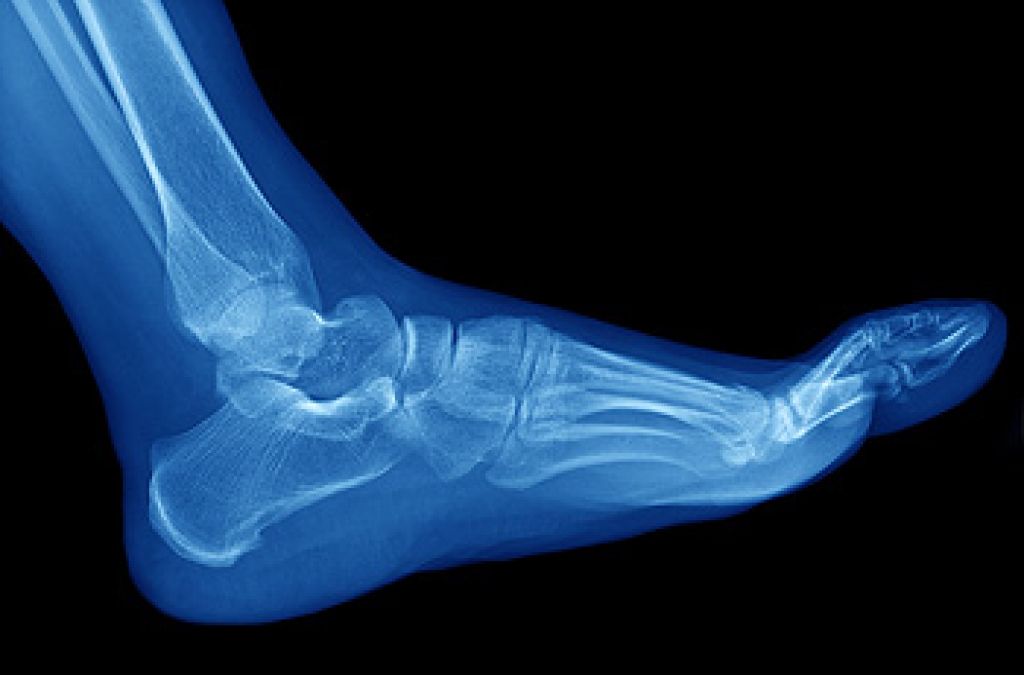

Skew foot, also known as serpentine foot, is a complex foot deformity often identified at birth or in childhood. It is characterized by a combination of abnormalities that affect the alignment and function of the foot. This condition involves a combination of forefoot abduction, where the front part of the foot turns outward, and hindfoot varus, where the heel turns inward. These alterations lead to a zigzag appearance of the foot, hence the name skew foot. Individuals with skew foot may experience difficulties in walking, balance, and may have discomfort or pain due to the abnormal pressure distribution on the foot. Treatment options vary depending on the severity and underlying cause of the condition. Conservative management includes wearing orthotic devices and special footwear to support and realign the foot. In more severe cases, surgical intervention may be required to correct the deformity and improve function. Early diagnosis and treatment are essential in preventing progression and maintaining mobility and quality of life. If your child has what appears to be skew foot, it is strongly suggested that you make an appointment with a podiatrist as quickly as possible for treatment.

Congenital foot problems are deformities affecting the feet, toes, and/or ankles that children are born with. Some of these conditions have a genetic cause while others just happen. Some specific foot ailments that children may be born with include clubfeet, polydactyly/macrodactyly, and cleft foot. There are several other foot anomalies that can occur congenitally. What all of these conditions have in common is that a child may experience difficulty walking or performing everyday activities, as well as trouble finding footwear that fits their foot deformity. Some of these conditions are more serious than others. Consulting with a podiatrist as early as possible will help in properly diagnosing a child’s foot condition while getting the necessary treatment underway.

- Vertical talus, where the talus bone forms in the wrong position causing other bones in the foot to line up improperly, the front of the foot to point up, and the bottom of the foot to stiffen, with no arch, and to curve out.

- Tarsal coalition, when there is an abnormal connection of two or more bones in the foot leading to severe, rigid flatfoot.